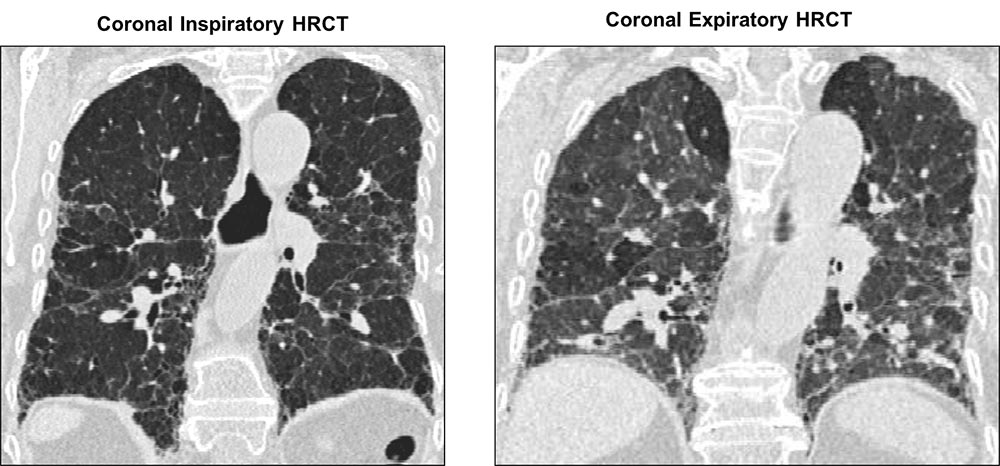

Coronal inspiratory and expiratory images from the same patient with chronic hypersensitivity pneumonitis. In the inspiratory cut, there is a subpleural predominance of architectural distortion and reticulation, regional volume loss, and traction bronchiectasis. In the expiratory image, there is obvious air trapping in addition to areas of mosaic attenuation.

Images courtesy of and used with permission from Jonathan Goldin, MD, PhD.